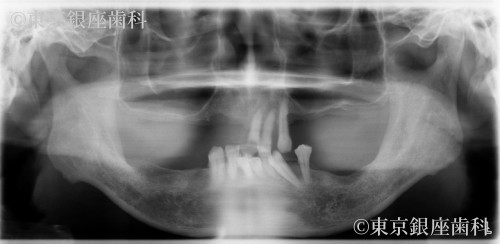

重度歯周病で骨が薄い状態から適切な固定を得て治療を進められた60歳代男性のインプラント症例

骨が薄く初期固定が困難と予測されたが、手術時に十分な固定が得られ入れ歯待機を回避。難症例ながら安定した治療結果に。

インプラント治療(骨吸収症例)